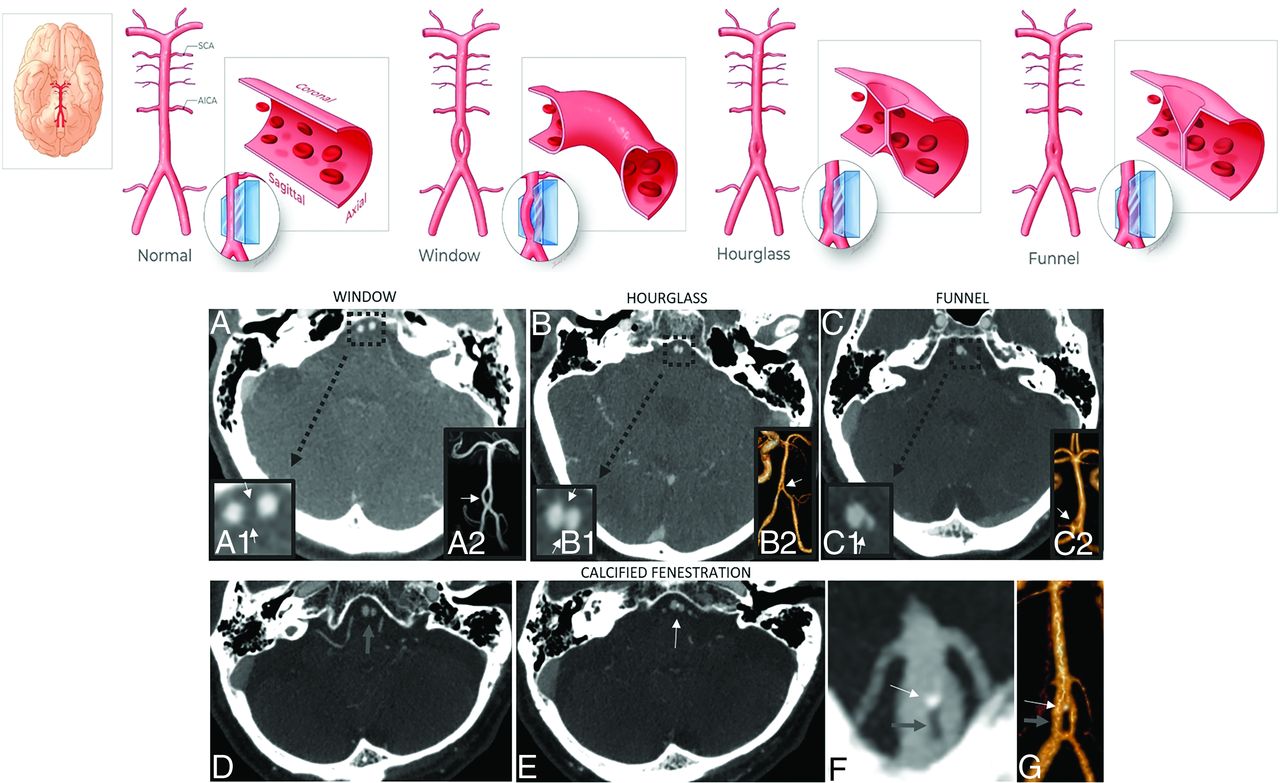

Of the 59 cases classified as a basilar fenestration, 27 had window-shaped fenestrations, 30 had hourglass-shaped fenestrations, and 2 had funnel-shaped fenestrations (Fig 1). The mean apertures of these 3 variations were 3.9 mm (range, 1.5–15 mm), 1.2 mm (range, 0.8–2.0 mm), and 1.4 mm (range, 0.9–1.9 mm), respectively. All the small basilar fenestrations without a window were associated with visible puckering/indentation of the vessel wall. Of the patients with basilar fenestrations, 53 were located in the inferior third (53/59, 89.8%); 4 in the middle third (4/59, 6.8%); and 2 in the superior third of the vessel (2/59, 3.4%). Of the 59 basilar fenestration cases, 17 had at least 1 other CTA or MRA with the imaging findings evident and unchanged on all studies. Of these 17 cases, 3 also had DSA and VasoCT (Philips Healthcare; conebeam CT with contrast) images of the posterior circulation confirming the basilar fenestration, also well-visualized with this technique.

Basilar fenestrations. I) Classification. Basilar fenestrations were classified as either window-, hourglass-, or funnel-shaped (upper row illustrations: printed with permission from Insil Choi, copyright 2020). Axial CTA images (A–C) and magnified axial CTA images focusing on the basilar artery fenestration (A1, B1, C1) and coronal 3D reconstructions of the posterior circulation (A2, B2, C2) in various patients depict different morphologies of basilar fenestration apertures. II) Fenestration with calcification. Associated calcification is evident in 3 of the basilar fenestration cases (3/59; 5.1%). Sequential axial CTA images in one of these patients demonstrate a fenestration (D, wide gray arrow) with a small nodular calcification along its superior aspect (E, thin white arrow), a finding better evident on coronal MIP (F) and 3D reconstruction (G) of the basilar artery (fenestration highlighted by a thick gray arrow, and the nodular calcification, by the thin white arrow).

Calcification was associated with intraluminal abnormalities in 16 patients. Associated calcification was evident in 3 of the patients with a basilar fenestration and in 13 of those with the basilar septations (Figs 1 and 3). With respect to calcified basilar septations, 5 of 12 linear septations were associated with calcification, while 8 of 9 nodular septations were associated with calcification.

A basilar intraluminal abnormality was detectable in 2.3% of patients on CTA. Of these, 1.7% had a basilar fenestration. To our knowledge, no previous study has documented morphologic differences in the aperture of basilar fenestrations. Our results reveal there are clear variations in the spectrum of size, morphology, and appearance of basilar fenestrations with less than half of our cases conforming to a typical window-shaped appearance, a little more than half of the cases exhibiting an hourglass shape, and only a few cases exhibiting funnel morphology depicted in our illustrations. Hourglass and funnel morphologies had smaller-but-measurable apertures in the vessel wall compared with window-type fenestrations. Furthermore, to our knowledge, no previous study has documented a congenital nonatherosclerotic pattern of calcification associated with basilar fenestrations, evident in 3 cases.